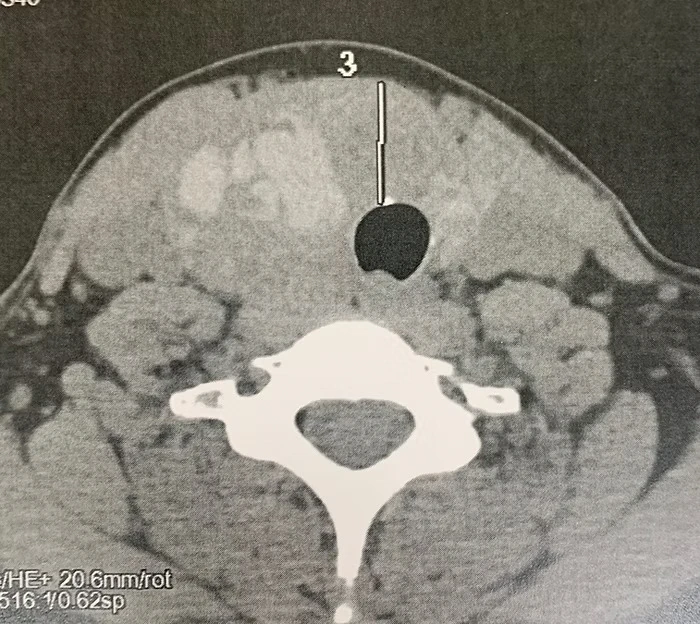

Case of a 37 years old Woman with 7cm Right Ishmic Nodes of the Thyroid Gland. Right Lobo-Isthmectomy was performed with the TOETVA procedure allowing no scar in neck.